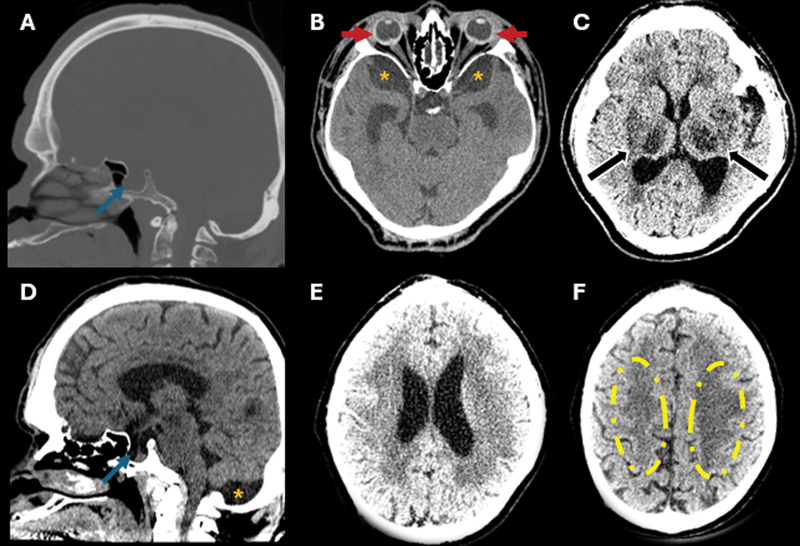

The hidden burden of lysosomal dysfunction: visual decline and microphthalmia in Hunter syndrome.